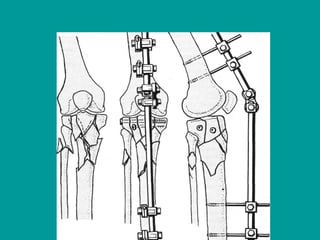

External Fixation

• Primarily used to treat severe open fractures, it

can also be indicated in closed fractures

complicated by compartment syndrome,

concomitant head injury, or burns.

• Its popularity in the United States has waned

with the increased use of reamed nails for most

open fractures.

• Union rates: Up to 90%, with an average of 3.6

months to union.

• The incidence of pin tract infections is 10% to

15%